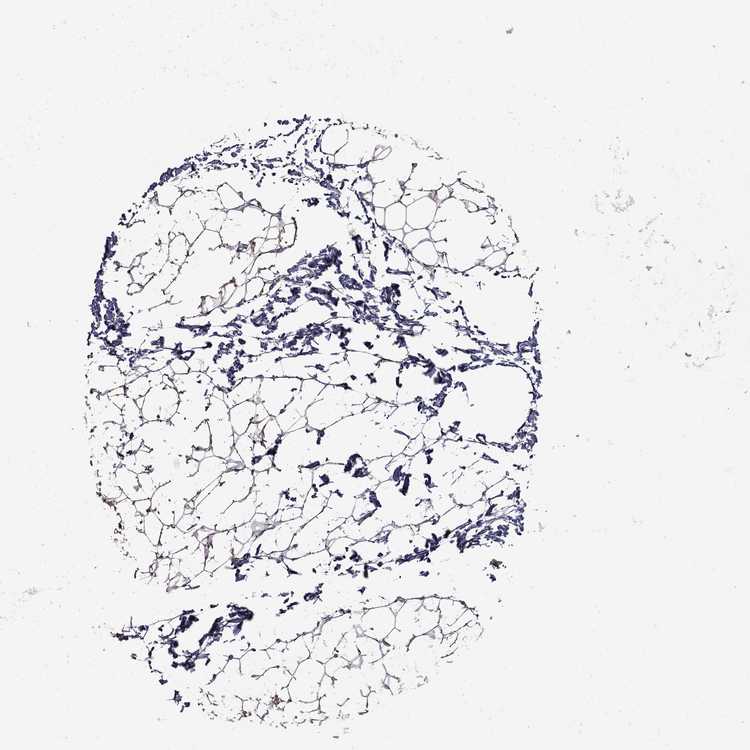

SOFT TISSUE 1 - Antibody stainingi

Antibody staining in the annotated cell types in the current human tissue is reported as not detected, low, medium, or high, based on conventional immunohistochemistry profiling in selected tissues. This score is based on the combination of the staining intensity and fraction of stained cells.

Each image is clickable and will lead to virtual microscopy that enables deeper exploration of all samples and also displays staining intensity scores, fraction scores and subcellular localization as well as patient and tissue information for each sample.

Antibody HPA078846

Fibroblasts Not detected